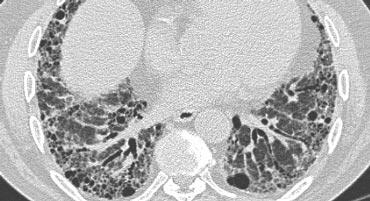

Centrilobular emphysema due to smoking. The periphery of the lung is spared (blue arrows). Centrilobular artery (yellow arrows) is seen in the center of the hypodense area.

Khí phế thũng trung tiểu thùy

- Loại phổ biến nhất

- Phá hủy không hồi phục vách phế nang ở phần trung tâm tiểu thùy

- Ưu thế ở thùy trên và phân bố không đều

- Liên quan chặt chẽ với hút thuốc lá.